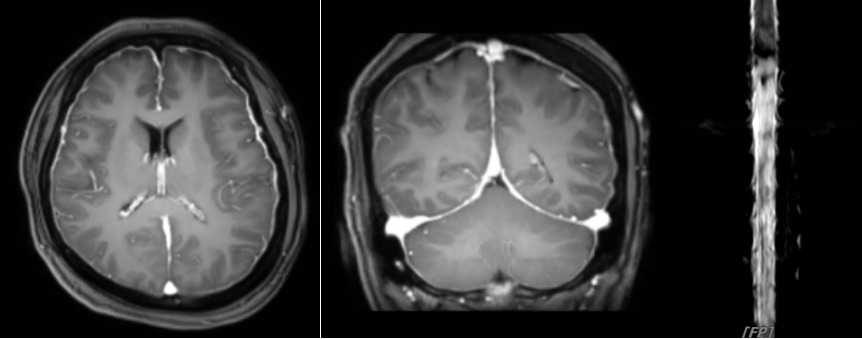

患者术前颅脑MR(左2)可见脑膜明显强化,并存在脑脊液漏(右1,脊髓水成象)

患者术后复查颅脑MR(左2)可见脑膜强化明显减轻,脑脊液漏消失(右1,脊髓水成象)